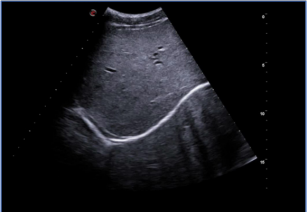

MyLab ™ OmegaVET- 实际应用

狗小肠

猫动脉

猫肾囊肿